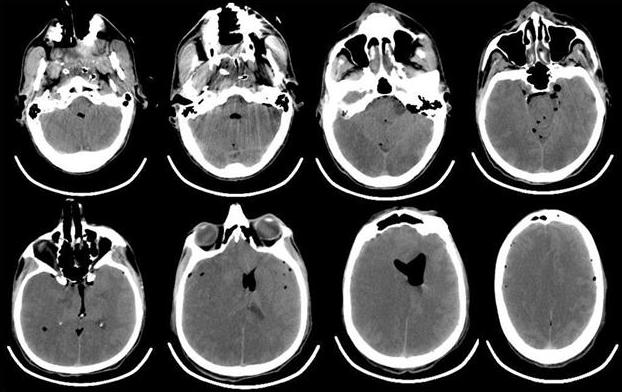

Рис. 4. КТ-головного мозга пациента, выполненная сразу после операции. Отмечается выраженная пневмоцефалия. В течение первых 12 ч после операции в структуре неврологического статуса у больного отмечалось нарастание общемозговой и очаговой неврологической симптоматики. Отсутствовала реакция на обращенную речь, болевое и струйное раздражение лица. При пассивном поднимании век взор неподвижный, двусторонний мидриаз без фотореакции. Роговичные, окулоцефалический и кашлевой рефлексы отсутствуют. Мышечная атония, арефлексия. Гемодинамика с тенденцией к артериальной гипотензии, несмотря на возрастающие дозы норадреналина максимально до 5 мкг/кг в минуту. Выполненная повторная КТ через 12 ч с момента поступления из операционной выявила диффузный отек головного мозга с отсутствием дифференцировки серого и белого вещества, пневмоцефалию (рис. 5).

Рис. 5. КТ-головного мозга пациента, выполненная через 12 ч после операции. Отмечается формирование выраженного отека мозгового вещества, с признаками латеральной дислокации. Остаточная пневмоцефалия. Снижение дифференцировки серого и белого вещества. В первые послеоперационные сутки состояние пациента оставалось без положительной динамики, сохранялись диффузная мышечная атония, арефлексия, артериальная гипотония на фоне применения высоких доз норадреналина. По результатам биохимического анализа крови: КФК 845 (N<200 Ед/л), ЛДГ 665 Ед/л (N=100-190 Ед/л), тропонин 18,76 (N<0,1 мкг/л). По данным допплерографии, артерии виллизиева круга не визуализируются. В артериях шеи (ОСА, ВСА, НСА и ПА) при цветном допплеровском картировании прокрашивание спонтанное, ЛСК=20 см/с. Повторно выполнена ЭхоКГ, которая показала: ФВ 31-33%, СИ=2,6 л/мин·м2, увеличение размеров Л.Ж. Значительное снижение локальной сократимости ЛЖ с формированием аневризмы в области верхушки и средних отделов ЛЖ с формирующимися неплотно фиксированными тромботическими массами, практически занимающими всю верхушку, и значительное снижение показателей насосной функции ЛЖ.